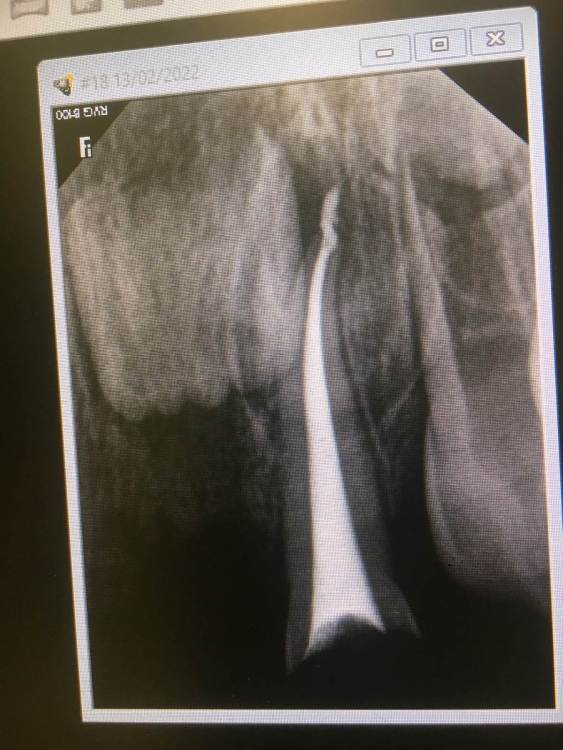

Здравствуйте, моей дочери 2 года. 12 дней назад ей пролечили под наркозом 3 верхних резца, пульпиты. На 2 зуба установили коронки, один реставрировали пломбировочным материалом. Сейчас прошло уже 12 дней, рядом с пролеченными зубками десна очень воспалены, красные и отечные. По рекомендации нашего врача мажем метрогил Дента, но улучшений нет. Подскажите, пожалуйста, в чем может быть причина? Неправильно установлены коронки? Есть Надежда, что воспаление пройдёт или необходимо будет ещё вмешательство?

Дело в том, что малышка не открывает рот врачам, любые манипуляции будут возможны только под повторным наркозом, чего очень не хотелось бы. Спасибо заранее за ответ.

51149846-34F3-49C2-BEB8-B065B6CC76A3.png09EDA12B-CD16-4E0D-B897-5C3D94E5A672.png